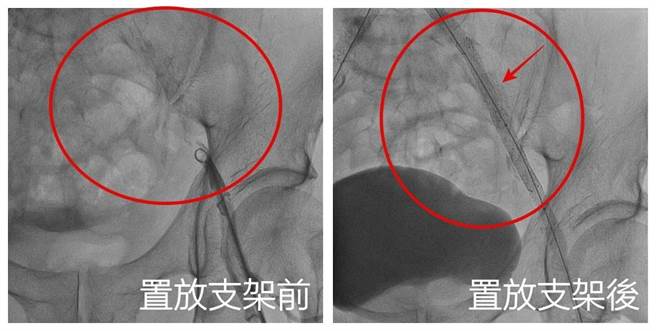

刘殷佐表示,患者肚脐上8公分处以下的主动脉及双侧总肠骨动脉完全阻塞,手术以导管打通置放5支支架,改善阻塞问题。(亚大附医提供/潘虹恩台中传真)

刘殷佐表示,与患者讨论后替其安排导管手术置放支架,先从患者的鼠蹊部及手臂动脉置放导管,接着在血管腔打通腹主动脉阻塞部位,最后将5支支架置放在右髂动脉,一举改善阻塞问题;患者术后5小时即可下床走动,术后第5天即康復返家,患者回诊时还透露,术后一併改善勃起困难,相当感谢。